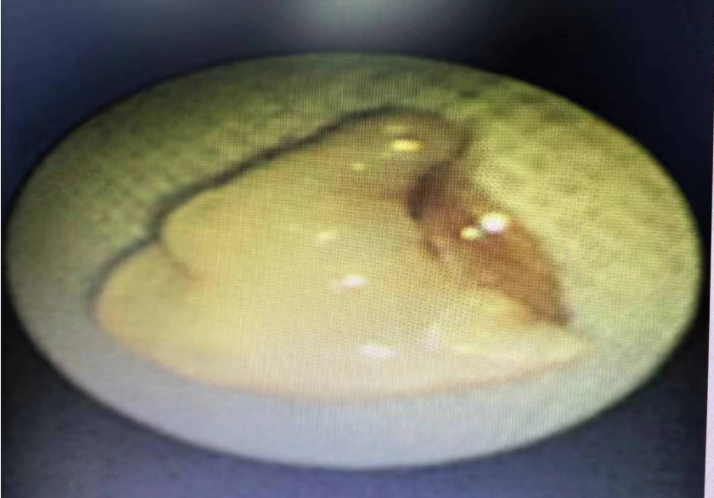

案例二

小炫,男,11岁9月,因反复咳嗽5年入院,完善胸部CT检查,影像学诊断右主支气管近段管腔内金属影,遂入院行“支气管镜气管异物取出术+肺泡灌洗术”,术中取出一枚锈迹斑斑的图钉,术后咳嗽症状消失。

(绿色箭头为异物)

(气管镜下取出图钉)